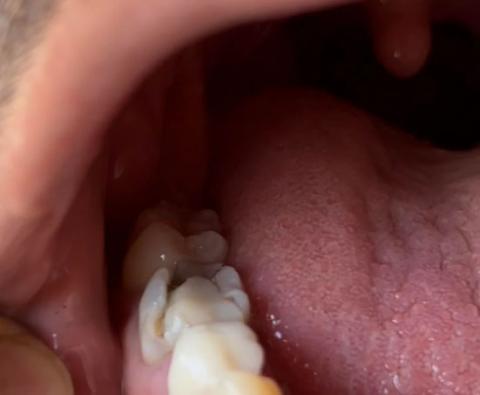

The image shows a posterior tooth located near the tongue side with visible enamel breakdown and a deep cavity. The tooth structure appears weakened, suggesting advanced decay and possible fracture.

-

Back tooth with broken enamel edge

Deep cavity extending into dentin

Darkened area indicating active decay

Inner (lingual) surface involvement

Food and bacteria retention area present

Surrounding soft tissue appears mildly irritated

Adjacent teeth appear intact